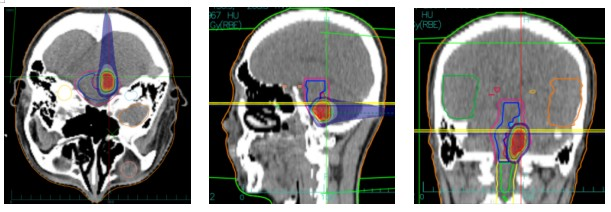

Carbon Ion Therapy Dose Distribution Map

Treatment Plan: Photon + Carbon Ion Therapy

First Course: Photon Radiotherapy

- Prescription Dose: 44 Gy in 40 fractions.

- Dose per Fraction: 1.1 Gy.

- Frequency: Twice daily.

Second Course: Heavy Ion (Carbon Ion) Radiotherapy

- Prescription Dose: 15.5 Gy (RBE) in 5 fractions.

- Target: GTV.